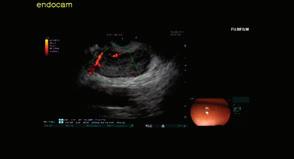

Доц. д-р Цветелина Тотомирова

60 РАДИОФРЕКВЕНТНА АБЛАЦИЯ НА ПАНКРЕАСНИ ТУМОРИ ПОД ЕНДОСОНОГРАФСКИ КОНТРОЛ Й. Петкова, П. Карагьозов, И. Тишков УРОЛОГИЯ